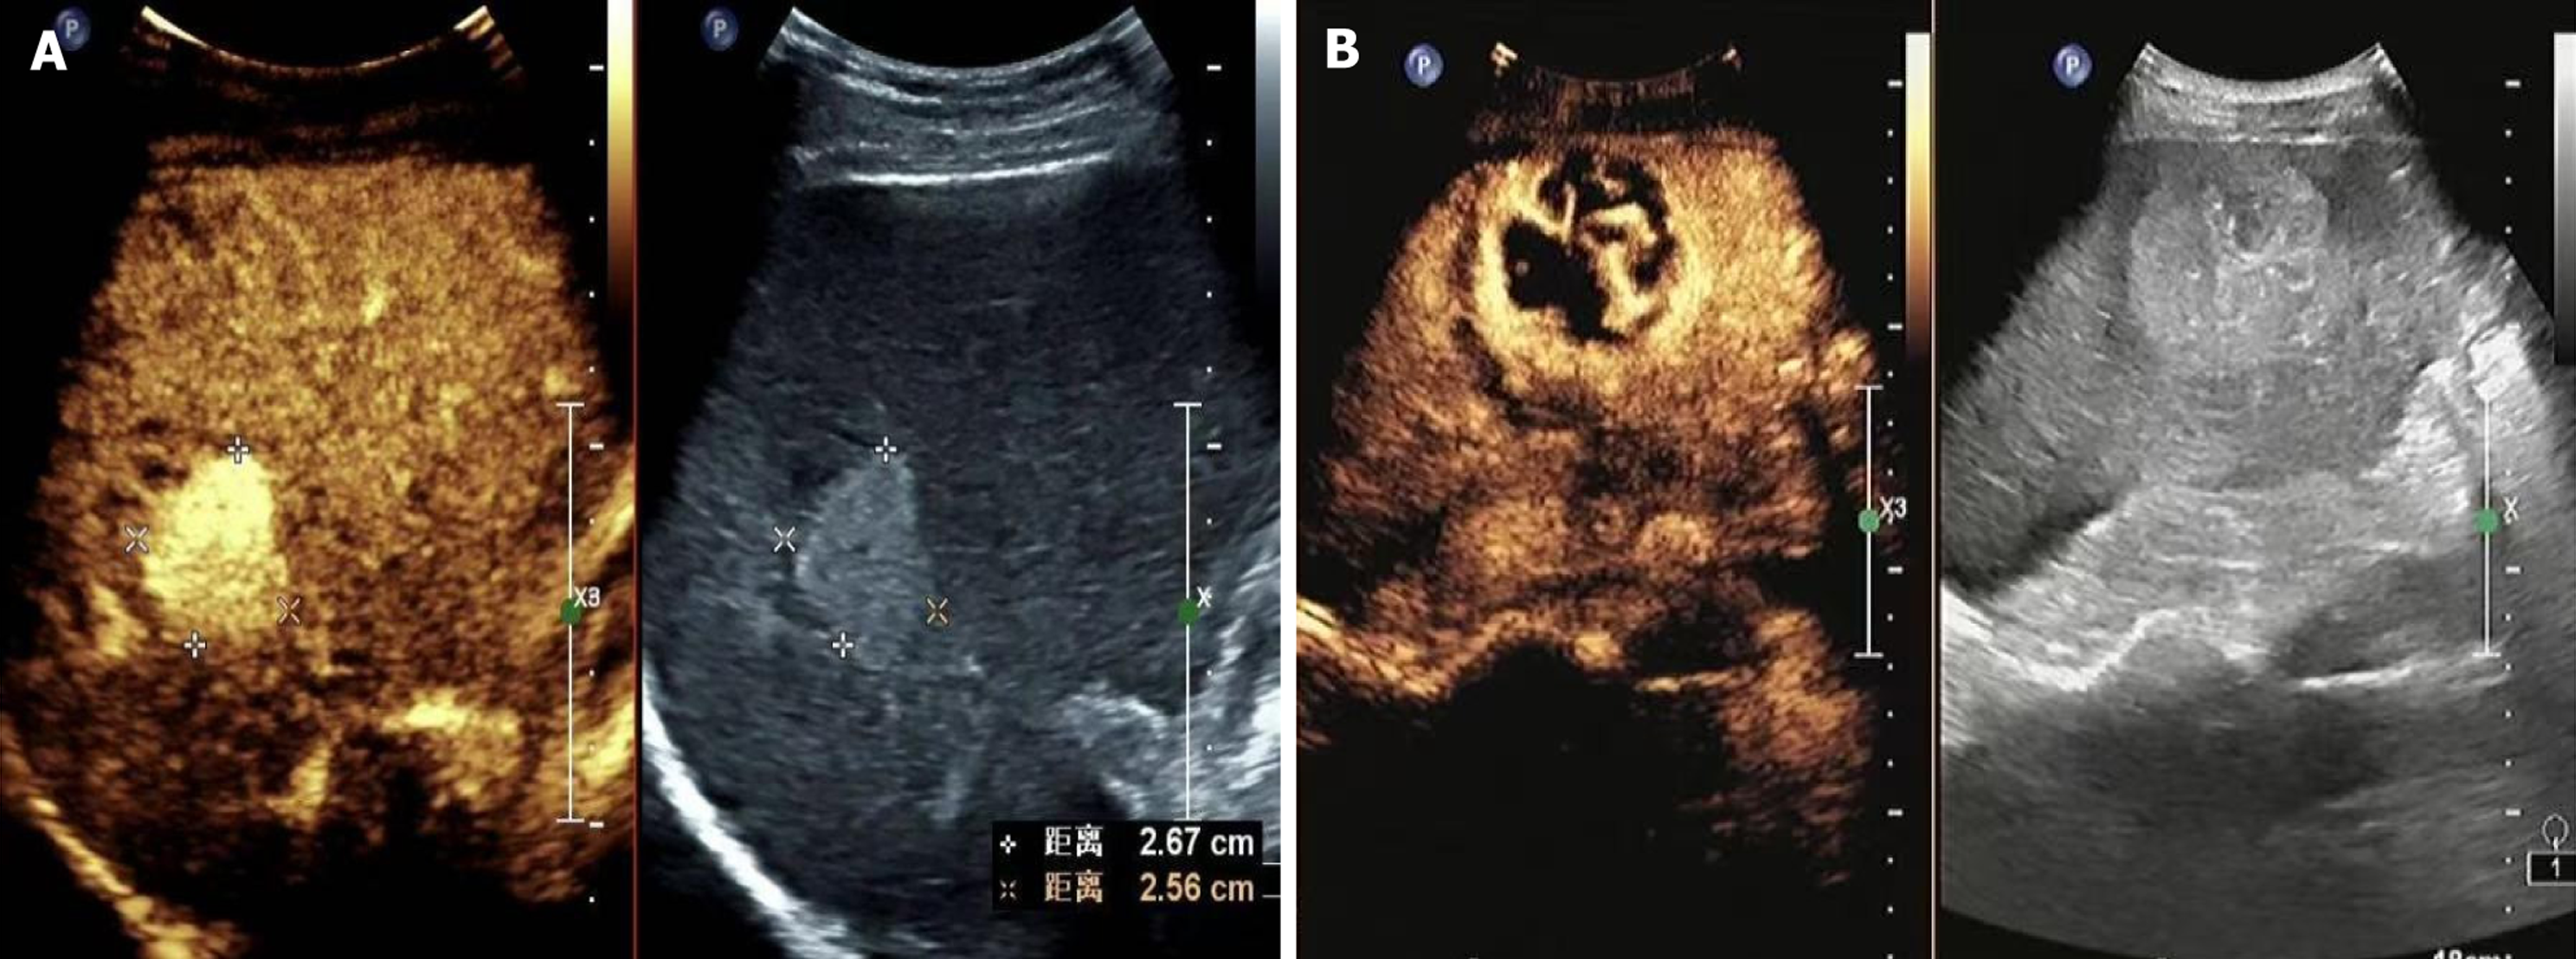

Figure 1 Good prognosis and poor prognosis.

A: Good prognosis. After contrast injection, the mass showed rapid and homogeneous enhancement in the arterial phase; B: Poor prognosis. A hyperechoic mass in the right lobe of the liver was examined using contrast-enhanced ultrasound. After contrast injection, the mass showed rapid and heterogeneous enhancement in the arterial phase, with peripheral ring-like and internal grid-like enhancements.